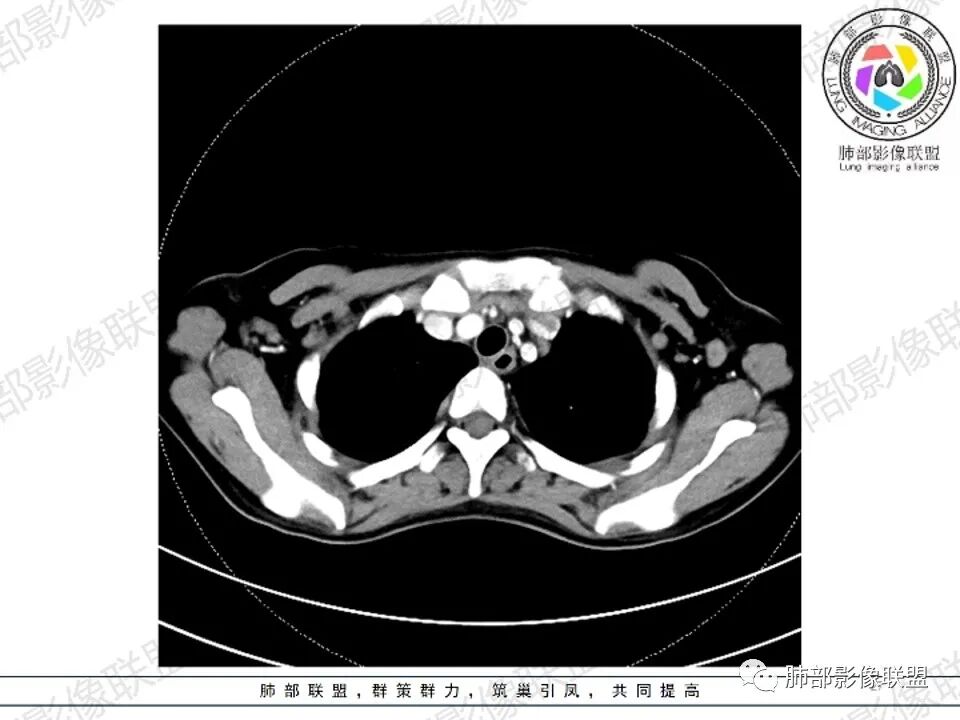

2.影像显示前纵隔不规则块状影,依势贴附心脏大血管旁,密度不均,边界不甚清楚,有结节融合感。

3.病灶轻度不均匀强化,可见血管穿行,散在液性低密度区。

双肺门未见肿大淋巴结。

4.双侧腋窝区见增大淋巴结,边界清楚。